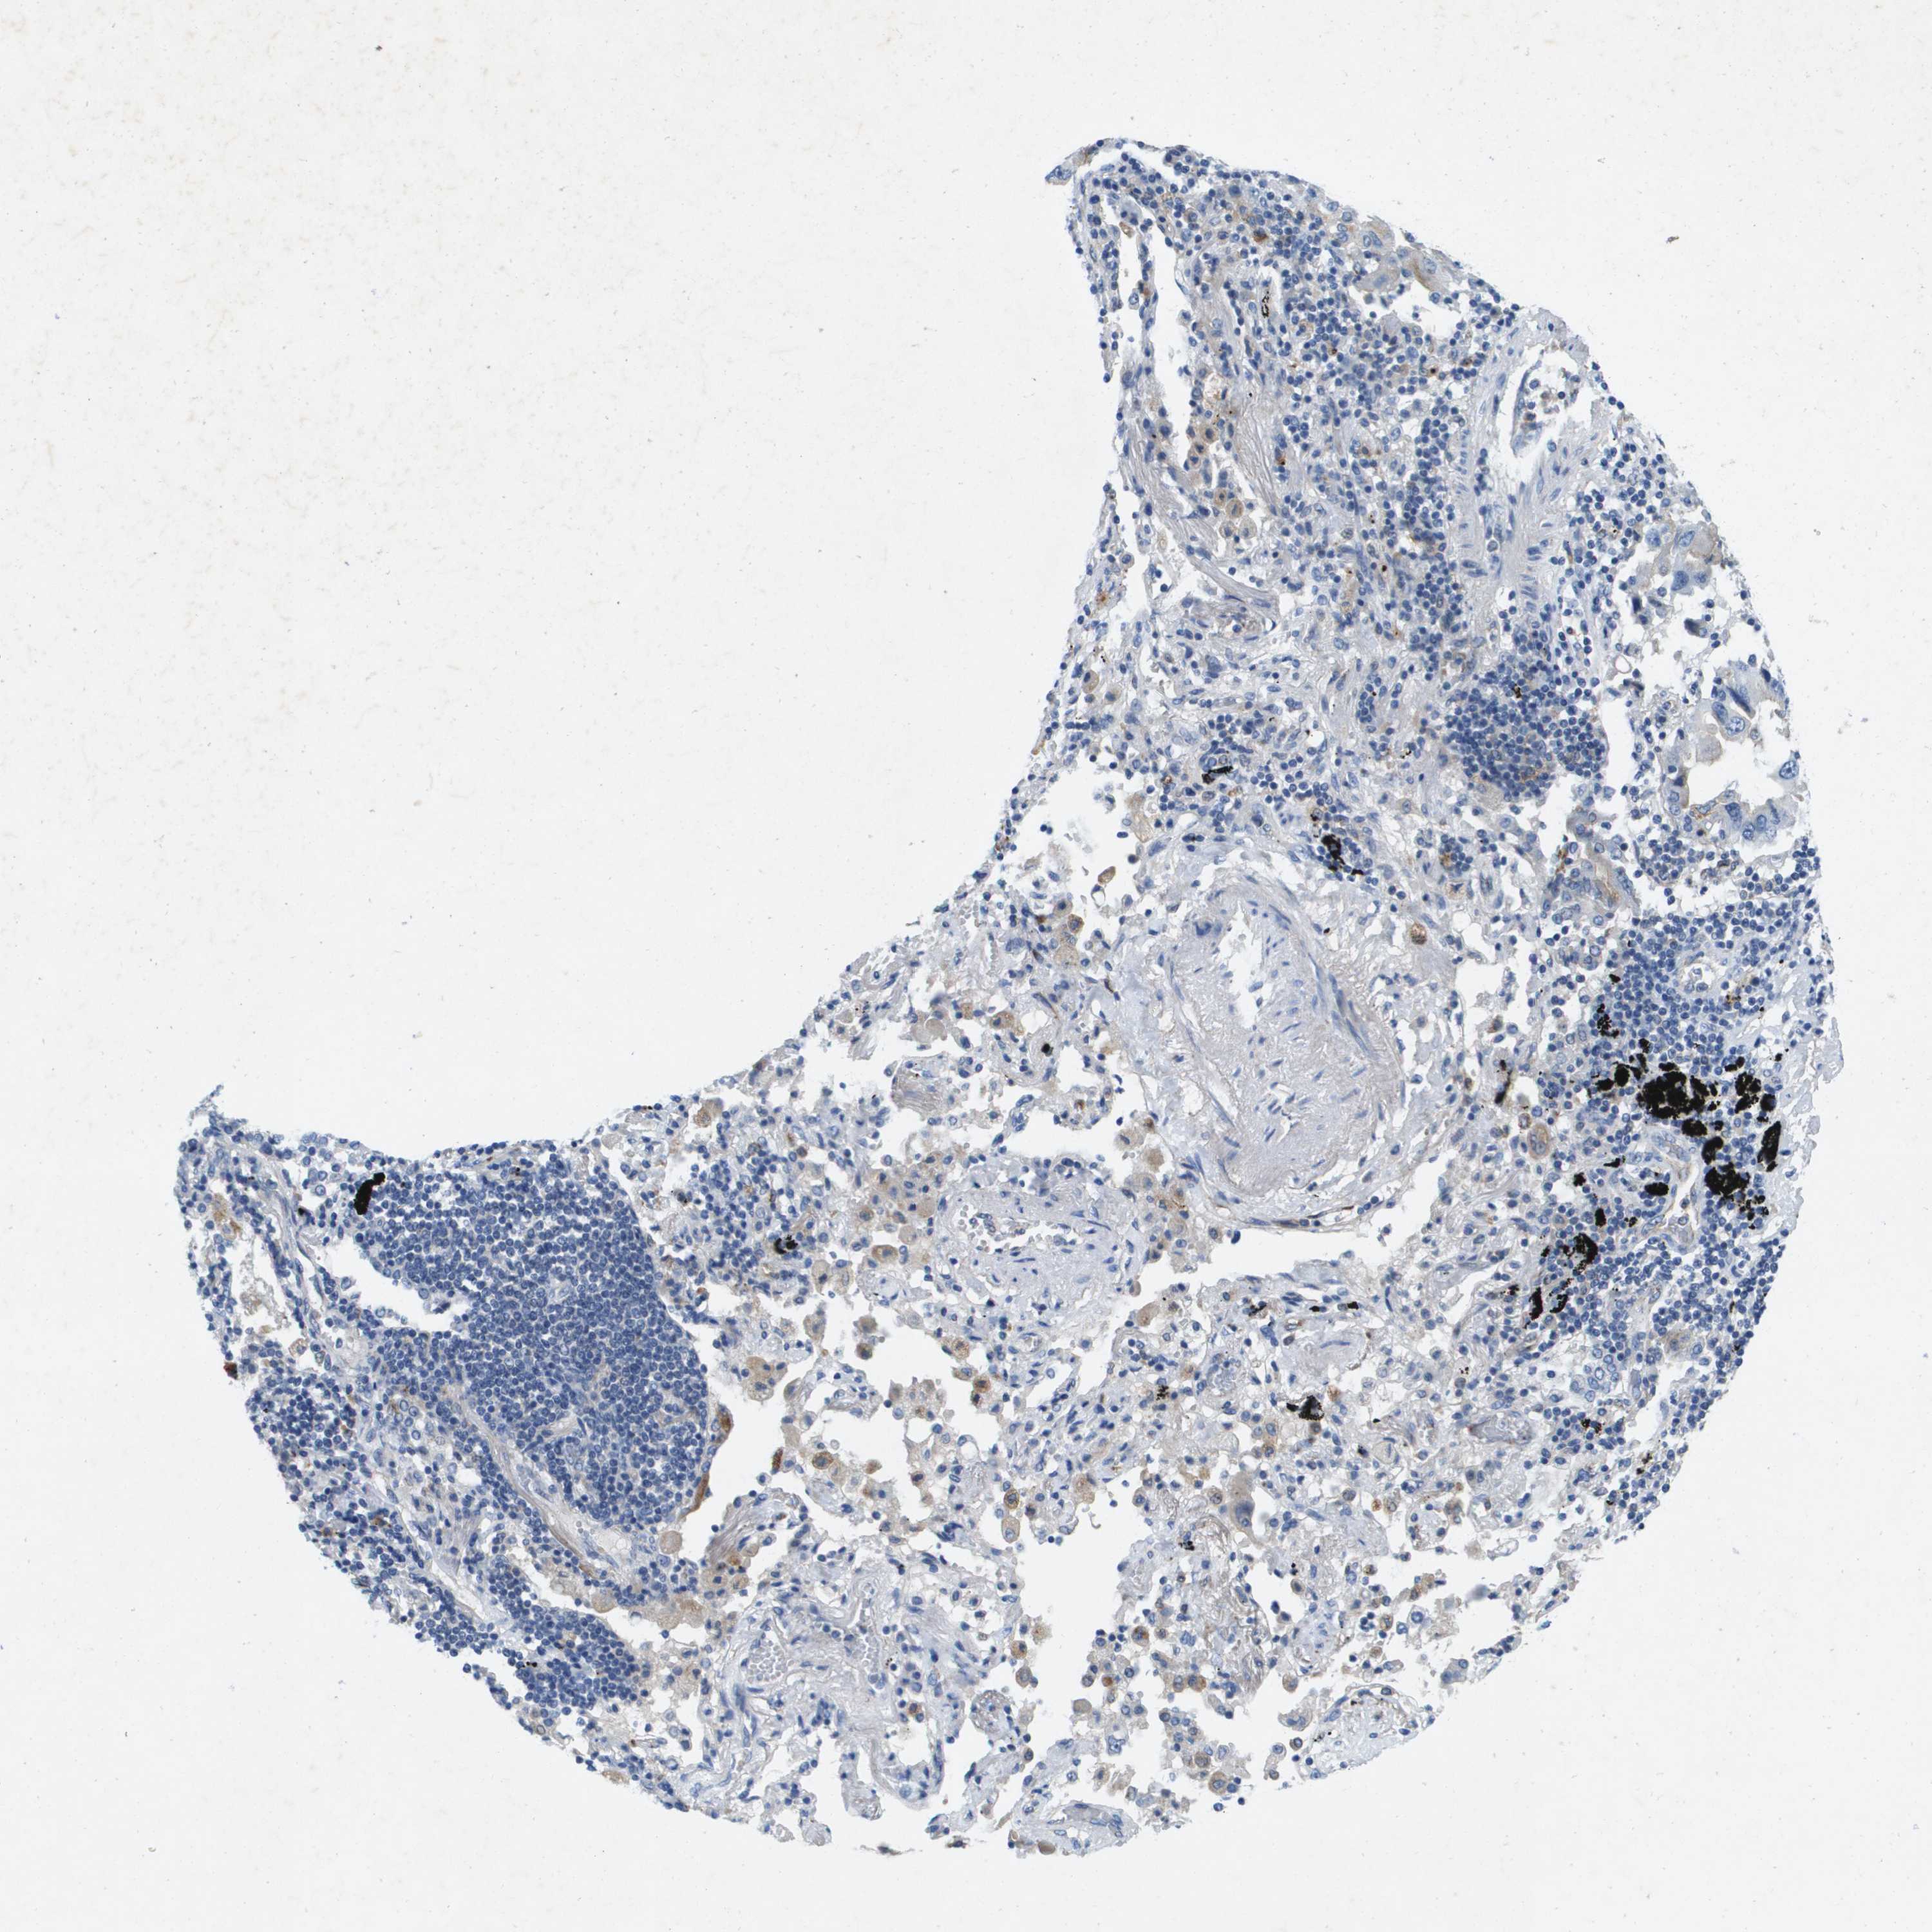

CANCER LUNG CANCER Show tissue menu

LUAD TCGA LUAD VALIDATION LUSC TCGA LUSC VALIDATION PROTEIN LUAD CPTAC PROTEIN LUSC CPTAC PROTEIN EXPRESSION

ANTIBODIES

AND

VALIDATION